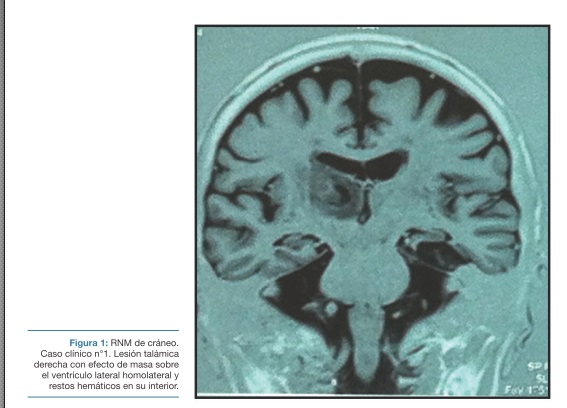

La resonancia magnética de cráneo muestra una lesión talámica derecha con efecto de masa sobre el ventrículo lateral homolateral y restos hemáticos en su interior (Figura 1).

Los hallazgos de la Resonancia Magnética de cráneo no permiten determinar la naturaleza de la lesión, pudiendo corresponder tanto a un hematoma parenquimatoso como a una lesión tumoral con componente hemorrágico.

El antecedente de hipertensión arterial orienta hacia el origen vascular de la lesión (8,10), sin poder descartar el origen neoplásico. No se planteó en este caso la posibilidad de que la lesión fuera de otra naturaleza.

Fue necesario recurrir a la realización de un PET scan para la confirmación etiológica, determinando que se trataba de un hematoma.